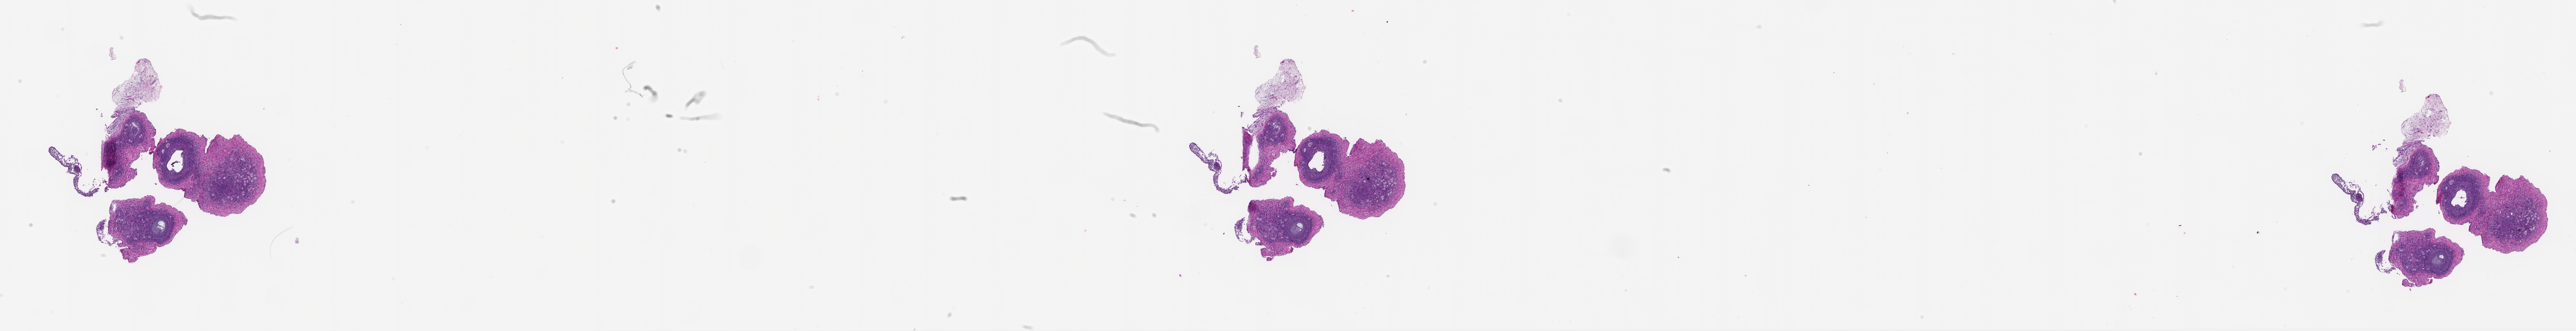

M. Zelinski, 2026, 'Zelinski Lab: Papio hamadryas Donor MZ_PH_39220 Ovary Right Slide 290', https://mother-db.org/MDB0000606, Multispecies Ovary Tissue Histology Electronic Repository, Retrieved: April 14, 2026

Genus: Papio (baboons)

Species: Papio hamadryas (hamadryas baboon)

Donor ID: MZ_PH_39220

Life Stage: aging

Age: 18 years, days

Stage of Cycle: luteal

Accession #: MDB0000606

Ovary position: right

Location: wholeOvary

Section thickness: 5 microns

Fixation: paraformaldehyde4

Stain: hematoxylinAndEosin

Immunohistochemistry: None

Experimental treatment: None

Other pathology: None